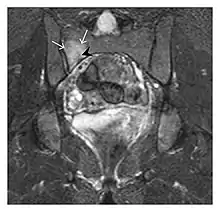

The sacrum is usually masked by overlapping bowel gas in conventional radiographs, and the subtle radiographic findings are usually nondiagnostic and even misleading. The characteristic "H" pattern has been correlated with biomechanical models of patient activities. The vertical parasagittal planes correspond to the region of maximal stress during walking, while the horizontal fracture develops later, secondary to the loss of lateral support by parasagittal fractures. MRI is the primary imaging technique in this case, with the most common MRI pattern showing bone marrow edema and a fracture line (Figure 12). Coronal views are quite contributive in sacral fractures, allowing the detection of the horizontal component, especially with fluid-sensitive sequences. Although the sacrum is the most commonly involved, pelvic insufficiency fractures are often multiple, and other typical locations should be mentioned.[1]

Proximal femoral fractures usually occur in osteoporotic patients, and their signs include subtle neck angulation, trabecular angulation, and subcapital impaction line. A frog-leg lateral view may be helpful if the greater trochanter is short enough. However, positioning can be difficult because of hip pain. In patients with strong suspicion of proximal femoral fracture and negative radiographs, MRI limited to coronal T1 W images and scintigraphy can be highly valuable (Figures 13 and 14). Such an option, with limited examination time, is cost-effective and allows reliable exclusion or confirmation of the diagnosis, preventing an unnecessary stay at the hospital or delayed treatment. Moreover, MRI helps to detect soft tissue abnormalities which are more frequently seen in femoral, acetabular, and pubic injuries than sacral lesions. Concomitant fractures are also frequently seen in typical pelvic sites.[1]

a

a b

b

Figure 13: Partial osseous avulsion of the gluteal muscles at the greater trochanter in a 59-year-old man who presented with the right hip pain without a history of trauma. Lauenstein view and anteroposterior and radiographs (not shown) did not show an obvious fracture line or disruption of bony contours in the acetabulum or the right femoral neck. (a) Coronal T1-weighted MRI displays an incomplete fracture line extending partially from the greater trochanter (arrow). (b) Coronal short tau inversion recovery MRI shows heterogeneous hyperintensity in the same region (arrow) as well as hyperintensity within the gluteus medius and minimus muscles (arrowheads) consistent with tissue edema and hematoma.[1]

a

a b

b

Figure 14: Subcapital insufficiency fracture in a 55-year-old man with a left hip pain without a history of trauma. Anteroposterior and Lauenstein view radiographs centered on the left hip do not show an obvious fracture line, but mild acetabular osteophytosis was noted consistent with hip osteoarthritis (not shown). (a) Coronal T1-weighted MRI shows a linear low-signal band through the femoral neck corresponding to a fracture line (arrowheads). (b) Bone scintigraphy shows focal uptake (arrow) corresponding to the fracture.[1]